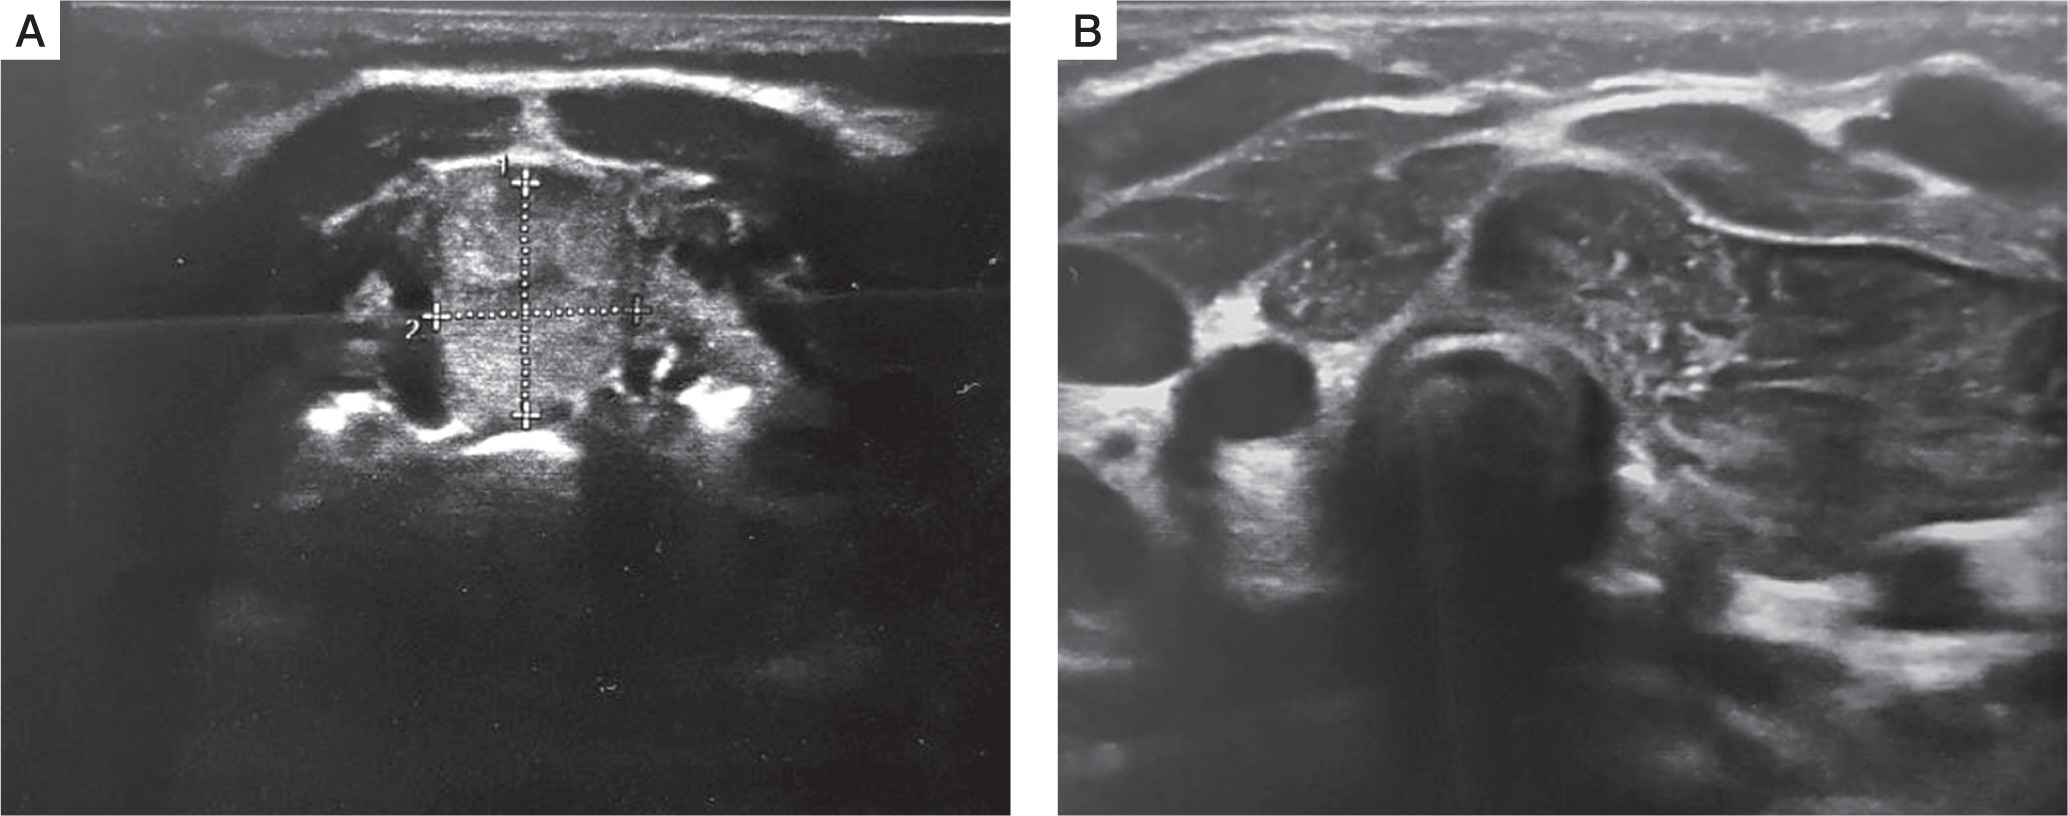

A female infant aged 3 months was admitted to the outpatient endocrine clinic due to suspicion of primary hypothyroidism. The TSH level in a random venous blood sample was 28 µIU/ml. The child was born at 38 weeks of gestational age by caesarean section, from the second pregnancy of nonconsanguineous parents. During pregnancy the mother was receiving levothyroxine in a dose of 50 µg/day due to elevated TSH level. Birth weight was 3700 g (0.97 SD), length was 57 cm (4.22 SD), and head circumference was 33 cm (–0.3SD). Apgar score was 10 in the first minute. The first result of a screening test for TSH was slightly above the upper limit of the normal range (TSH 19.94 µIU/ml; N < 18 µIU/ml), but when repeated on 6th day it was normal (9.96 µIU/ml; N: < 12 µIU/ml). Postpartum the mother started to breast feed. There was no need to continue the levothyroxine supplementation. An additional TSH test was performed because of the mother’s concerns about the previous positive result. At admission the body weight 7.1 kg, which was proper for body length (67 cm), both above the 97th percentile. The anterior fontanelle’s size was 1 × 1 cm. The heart rate was 110 bpm. The child did not present any signs of abnormal thyroid function. The neurological development was appropriate for the child’s age. No infection occurred during the first 3 months of life. The diagnosis of primary subclinical hypothyroidism was established on the basis of a blood test performed in the endocrine clinic: TSH 26.3 µIU/ml (N: < 10 µIU/ml), with FT4 14.7 pmol/l (N: < 10–25 pmol/l) and fT3 6.9 pmol/l (N: 3–8 pmol/l), and Tg (thyroglobulin) 455 ng/ml (N: 3.5–77 ng/ml). Neck ultrasonography (US) revealed ectopically located thyroid tissue in the submandibular area (Fig. 1). Scintigraphy with technetium-pertechnetate (99mTc) confirmed submandibular thyroid gland with empty fossa (Fig. 2). The treatment with liquid levothyroxine in the daily dose of 2 µg per kg of body weight was introduced. The control examination after 2 weeks revealed the normalization of TSH level (7.56 µIU/ml) with fT4 (16.7 pmol/l), and fT3 (6.9 pmol/l) within normal range. In the US control after one year, the dimensions of the ectopic thyroid gland decreased (11 × 12mm), and morphology and biochemical tests were within normal range. At 12 months of age the child showed normal psychomotor development. The dose of the levothyroxine was 3 µg/kg/day.